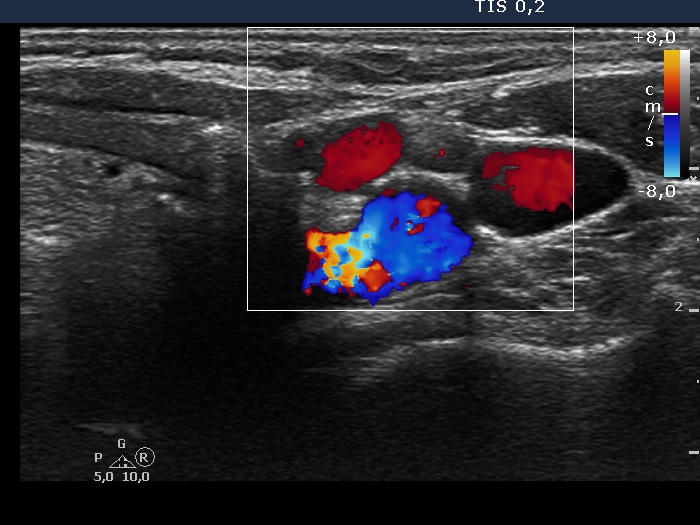

Ultrasonography: We could not find thyroid parenchyma. A small lymph node was present lateral to the left thyroid bed. The hilum was absent.

Cytology was performed and resulted in benign reactive lymphoid lesion.

Wash-out thyroglobulin was 0 ng/mL.